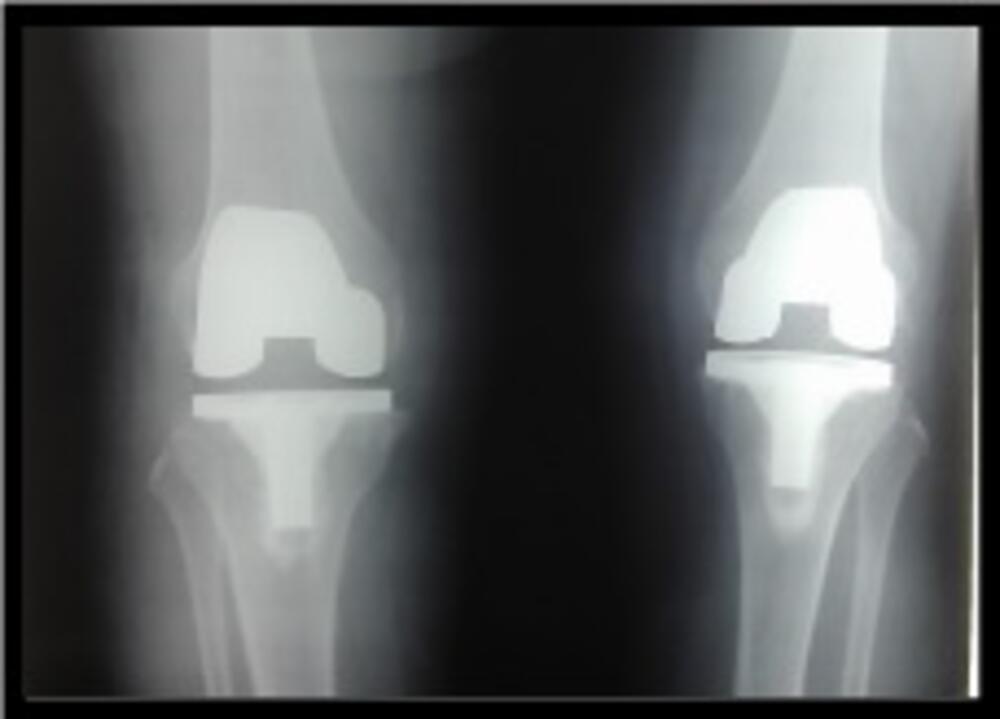

Dr Radoslav Barjaktarović, ortopedski hirurg, već više od 20 godina izvodi totalne artroplastike koljena– zamjenu zgloba koljena ugradnjom endoproteze. Izvodi primarne, revizione kao i parcijalne artroplastike.

Bavi se veoma uspješno zamjenom oba koljena u jednom aktu – bilateralna artroplastika koljena tokom jedne procedure. Posjeduje iskustvo od nekoliko stotina uspješno izvedenih operacija zamjene oba koljena tokom jedne operacije.